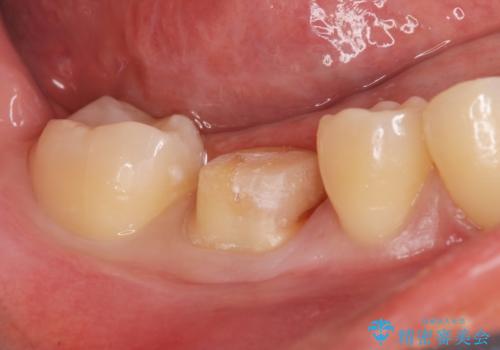

食べ物食べたら歯が欠けた。

- 過去に退院で治療した詰め物が欠けたことにより来院。

古いプラスチックの樹脂、虫歯を全て取り除き